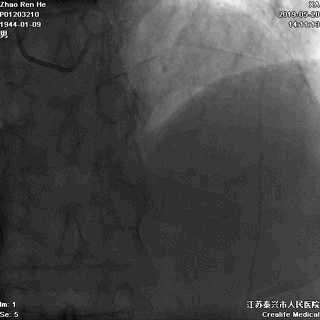

LAD发出第一对角支后即慢性闭塞

闭塞入口显示不清

闭塞出口处血管相对比较“健康”

LAD闭塞段小于20mm

LM分叉相对正常

未见提供LAD的逆向侧枝

推测LAD存在前向微孔道